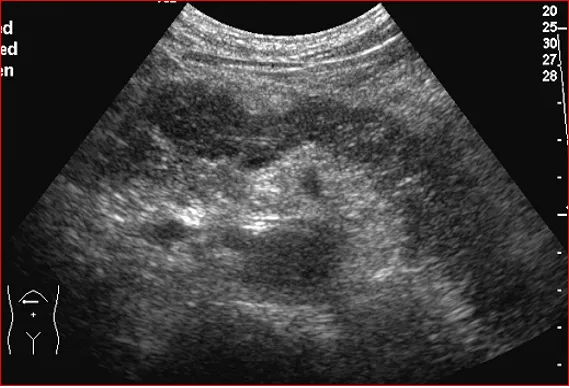

上腹部横切显示胰尾部占位压迫脾静脉呈“Z”形

● 灰阶超声表现

1.直接征象

①小于2cm的肿瘤多为均匀低回声,圆形,与正常组织无明显界限,无包膜,后方回声衰减不明显

②随肿瘤增大肿块内回声不均匀,部分可有钙化、液化、或呈高回声改变,肿物边界不清,呈浸润性生长,形态不规则,后方回声衰减

②肿瘤附近的血管被推移、挤压、变形或被肿瘤包绕

直径4cm以内的胰腺癌内很少能检测出血流信号,肿瘤增大时可于周边或内部检出少许血流信号,胰腺周围大血管较多,血管可被推移、挤压、浸润,或管腔内癌栓形成,CDFI有利于大血管的检查及鉴别。